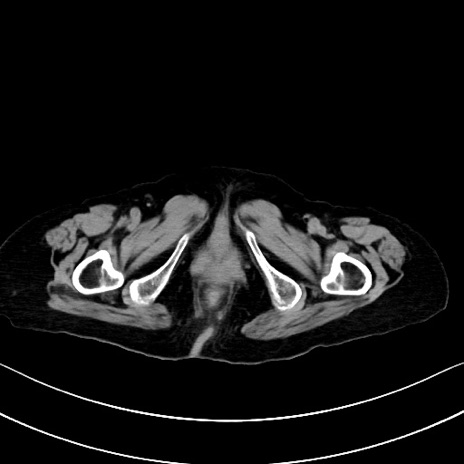

横断像

他院CT